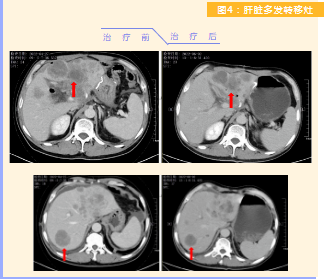

患者完成1周期治療后,上腹部疼痛癥狀基本消失,梗阻性黃疸癥狀緩解,腫瘤指標(biāo)下降(圖1),肺部多發(fā)轉(zhuǎn)移灶消失和縮?。▓D2),雙肺門淋巴結(jié)縮?。▓D3),肝臟多發(fā)轉(zhuǎn)移灶縮小(圖4)。